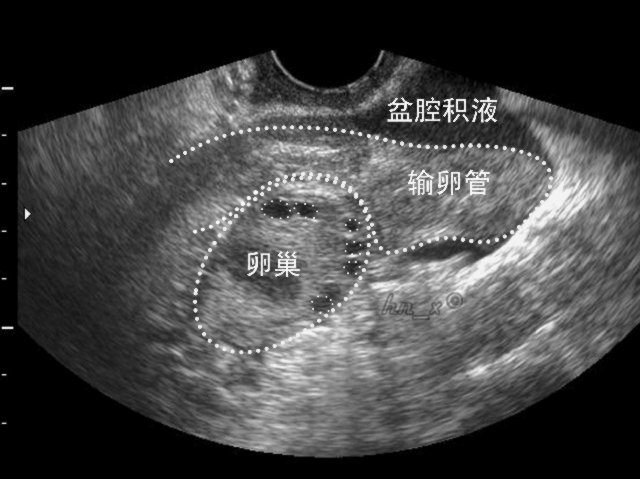

盆腔积液的超声图像

在正常情况下,腹膜具有吸收和分泌的功能,使腹膜腔内存在少许浆液,以减少腹腔脏器间的摩擦。而这些浆液通过脏器间的摩擦后,往往会积聚在腹腔最低的部位——盆腔;在B超检查报告上,则会将这最低的部位详细描述为“子宫直肠窝”或“子宫直肠陷窝”(由腹膜围绕着直肠前壁向下移行于阴道后穹隆,再向前向上移行覆盖子宫颈和子宫后壁,形成了直肠和子宫之间的腹膜凹陷)。所以,当女性平卧做B超检查时,盆腔内有少许积液是正常现象

另外,由于卵巢表面是没有腹膜覆盖的,在正常情况下,两边的卵巢每个月会轮流排卵。当卵巢的优势卵泡破裂时就会把卵泡液排进腹腔,从而集聚在子宫直肠窝,少则形成2~3毫升,多则10毫升。同样,每一个月月经来潮时,少量经血和子宫内膜碎屑也可以从子宫腔里逆流进入输卵管,从而“倒流”入腹腔内,最后再往腹腔最低处的盆腔处汇聚成积液。